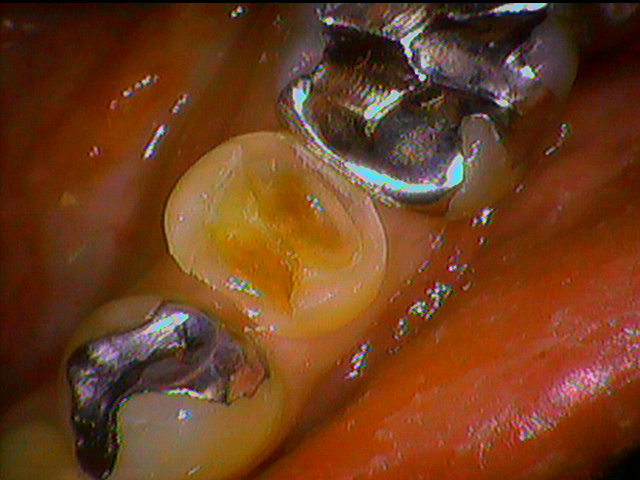

歯周組織の改善には歯周ポケットと呼ばれる歯肉の中に深さを測る小さい器具を患者さんに痛みがないようにいれていきます。前回の数値よりも良くなっている結果が分かりました。

見た目の歯ぐきの状態も綺麗に改善回復していました。患者さん本人も歯ブラシのやり方一つで歯ぐきから血が出なくなったと喜んでいました。月1回の歯周病予防のためのメンテナンスを受けたいとのことでした。